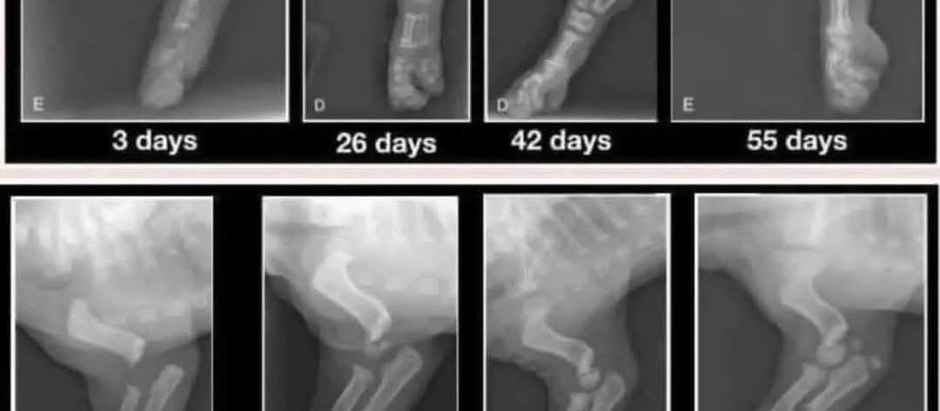

Bringing home an 8-week-old puppy is exciting, heart melting, and if we're being honest at times, it may be overwhelming. But here's something every new puppy needs to understand: You did not bring home a "small dog" You brought home a baby. And their body is far from being fully developed! Puppies Aren't Built Like Adult Dogs At eight weeks old, a puppy’s bones haven’t fused, their joints aren’t stable, and much of their structure is still made of soft, flexible cartilage. T